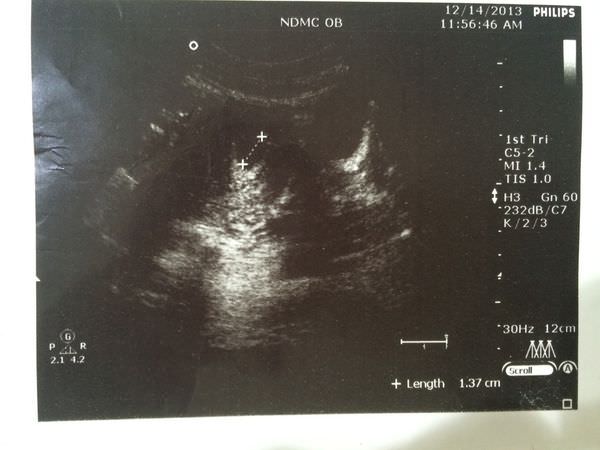

第二次(12/14)看診

今天主要是來確認胚胎位置!!!!不斷摸著肚子叫寶寶一定要出現在對的位置!!!

一樣照舊去照了超音波~~~

結果

竟然跟上週一樣!!!找不到?!?!怎麼可能~~~當下真是有種想掉淚的感覺><

進了診間,醫生說還是沒照到耶!!!我們一臉失望><

好吧!!!我等下親自幫妳照~~~如果沒照到可能就要有心理準備!!!Shit!!!

好險寶寶只是跟我們開開玩笑!!!!醫生沒找多久馬上就找到了!!!

我們整個都放心了~~~不自覺嘴角都上揚了><

心想那個超音波師真的要再加強啦!!!!想嚇死多少父母???

我就知道寶寶跟我們玩捉迷藏

就這樣~~~拿到了第一張超音波照片!!!那時候寶寶才1.37CM~真的很小><這時候大約才5~6週左右